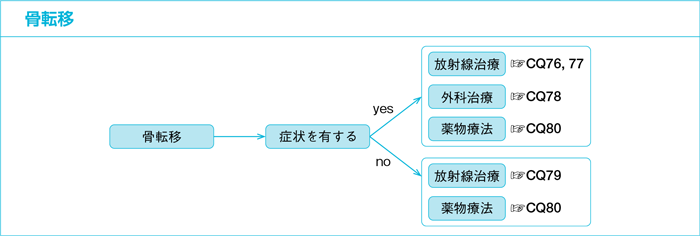

前立腺がんの骨転移治療の選択肢が拡大 医療ニュース トピックス

腎臓がん 腎細胞がん の転移 再発 がん情報サイト オンコロ